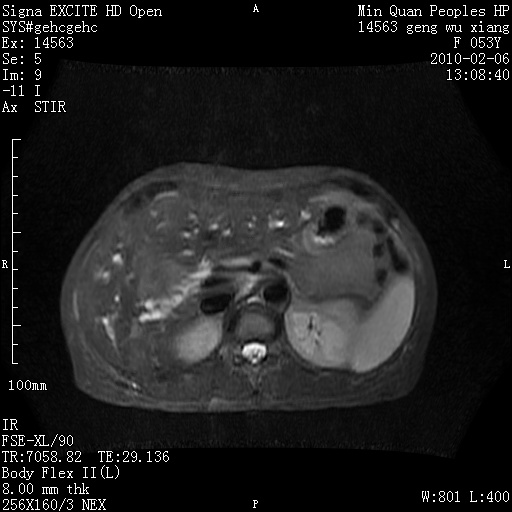

标题: MRI2762:胆道梗阻原因?

f,53y,全身黄染多日。

高位胆道梗阻 胆管癌可能性大

支持 高位胆道梗阻 胆管癌可能性大。